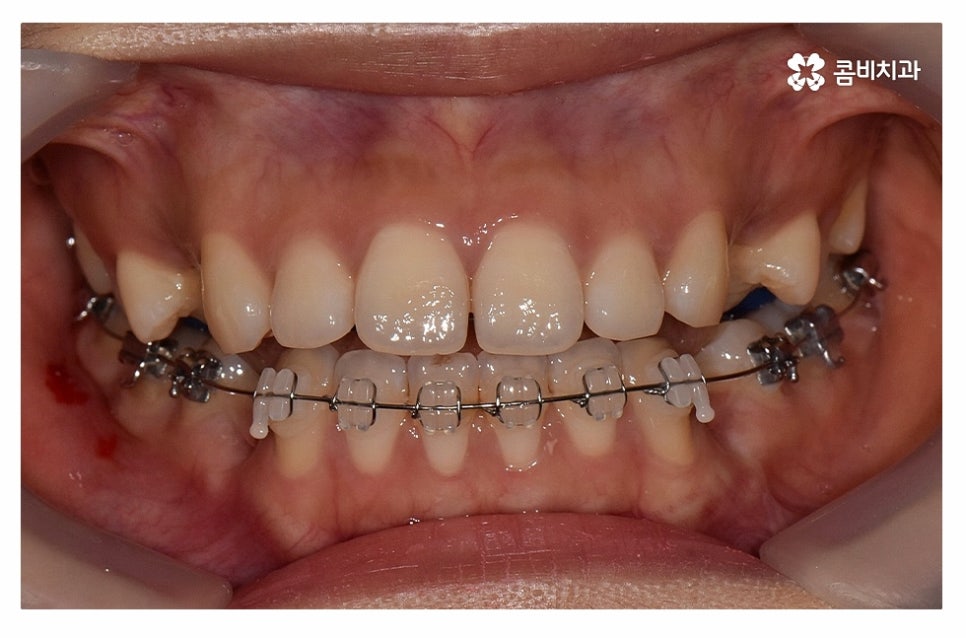

위 환자분의 경우 정면에서 보이는 치열은 가지런한 편이지만

치아가 돌출되어 돌출입으로 고민했던 사례이며

치아의 이동 공간 확보를 위해 발치 교정을 진행한 사례라고 할 수 있어요.

윗니는 설측교정으로 진행하고 아랫니는 일반적인 순측교정으로

치료를 진행하는 방식을 콤비교정이라고 부르고 있는데요.